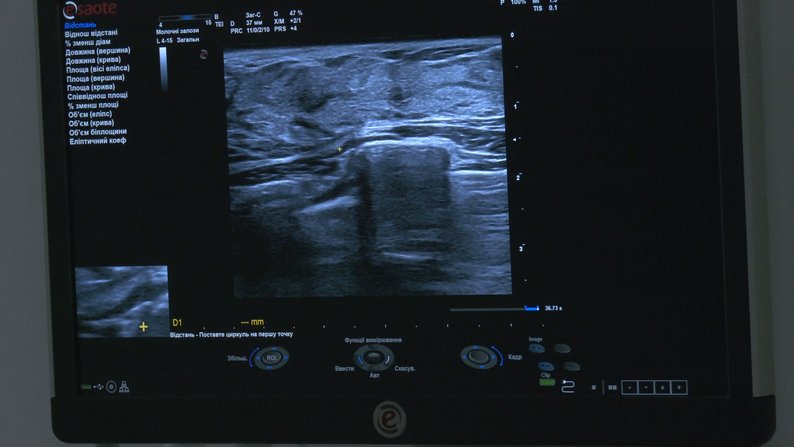

Зображення на моніторі УЗД-апарату. Суспільне Вінниця

Лікар-мамолог Андрій Клекот сказав: аби запобігти захворюванню, жінки після досягнення двадцятирічного віку мають щороку проходити огляд у мамолога та робити УЗД молочних залоз, а після 40 років — мамографію.

Пройти безкоштовне обстеження та зробити УЗД молочних залоз в регіональному центрі онкології можна за електронним направленням від сімейного лікаря.